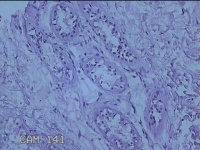

右侧腋窝皮肤

性别

女

年龄

25岁

临床诊断

双侧腋臭

一般病史

发现双侧腋下异味7年。

标本名称

大体所见

灰白暗红色梭形皮肤组织7x2.3x0.8cm一块,表面糜烂,切面灰白暗红色,质软。

图2